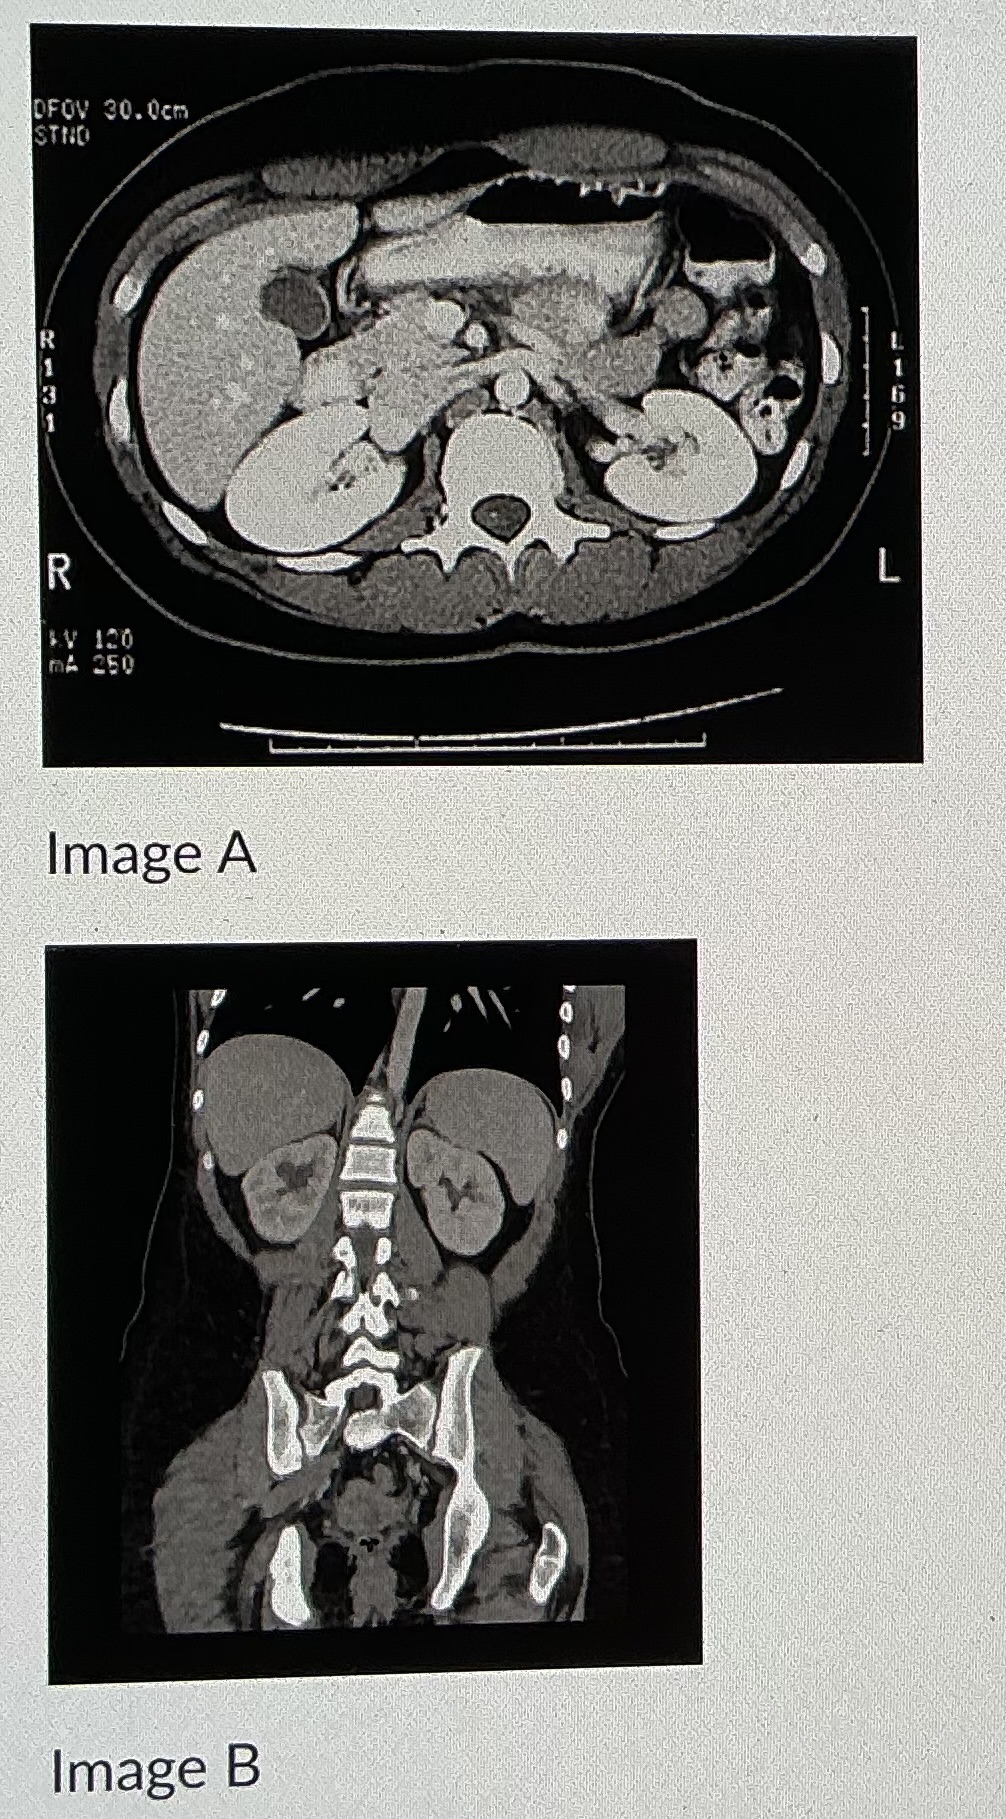

When you are looking at a CT scan, it is as if you are looking

from the feet up to the head

On a CT, you will see a “hat” on top of each kidney. This is called the

adrenal gland

Image B shows an image taken in what plane

coronal